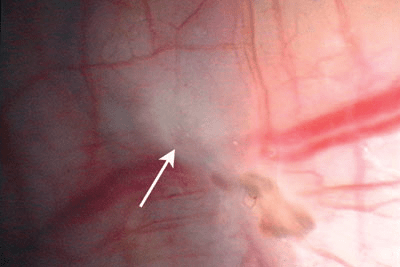

Figure 4 : Avec le temps, des lésions glandulaires incolores (flèches) peuvent secréter une substance paracrine pouvant déstabiliser les capillaires voisins et provoquer une hémorragie. Une légère fibrose du péritoine peut également survenir et masquer en partie les vaisseaux présents sous le péritoine. Une angiogenèse débutante est visible près du milieu de la zone hémorragique, conséquence de la sécrétion d’un facteur de croissance de l’épithélium vasculaire (VEGF).